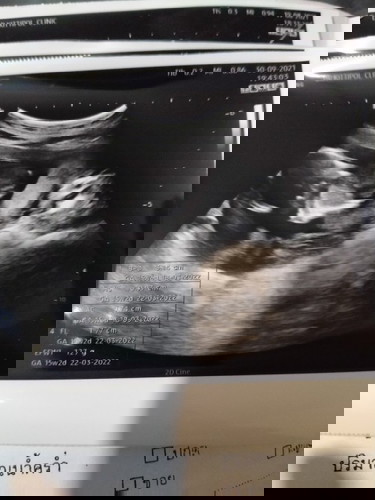

EFW ค่ะ วิธีการอ่านใบซาวด์อื่นๆ จิ้มเลยค่ะ 👉🏻 https://community.theasianparent.com/q/วันนี้_หม่ามิ๊_มาแชร์_การอ่า/3571668?d=ios&ct=q&share=true

Đọc thêm127กรัมค่ะแม่